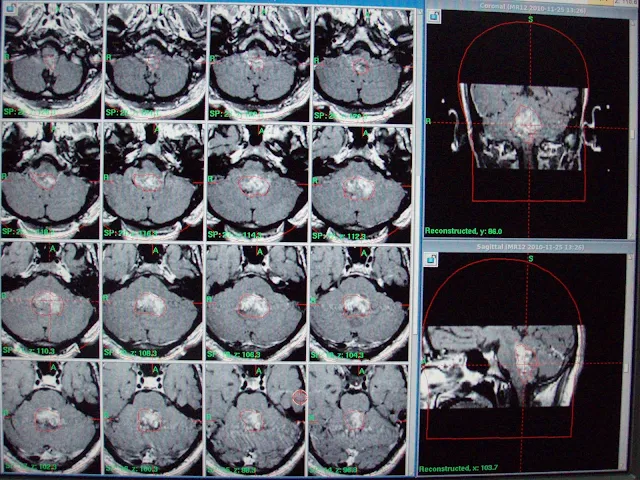

On referral, he had presented some improvement in headache and vomiting and significant improvement in blurring of vision. Clinical examination had revealed no obvious neurologic deficit. MRI brain spectroscopy had revealed markedly elevated Choline levels up to 399. Patient has referred us for the management with GKSRS. Risk of GKSRS explained all in Urdu along with requirement of strict follow up. These agreed upon wished to proceed. He had treatment with following prescription,

Target | Location | Prescription | Volume |

A | Ependymoma. | 12Gy @ 50% | 18.6 cm³ |

Multiple isocenters with 18, 14 & 8 mm collimator used in APS mode. He had discharged on tapering doses of Dexamethasone and advised follow up after 3 months